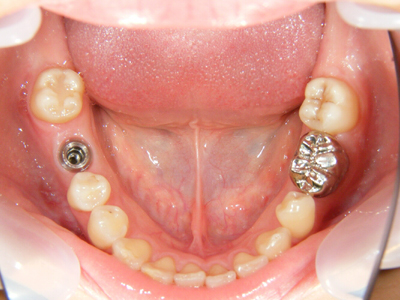

6. 施術前上顎観

上顎左右の8番(移植歯としての利用は断念)、および左上4番の抜歯した後の上顎写真です。これを見て思うのは、1歯レベルではとても良質の歯をしているのに、6番(6歳臼歯)が失活(神経を取った)又はかぶせ物がなされていることから、小学校から高校くらいまでの間は混合歯列期(乳歯と永久歯が共存している時期)や最初に萌出する6番の時期に、歯科的なアプローチが結果的に不十分だったことです。

7. 施術前下顎観

下顎も1歯レベルでは本当に良い歯質をしています。残念なのは右下6番部の欠損(残根は抜歯済み)と、左下に存在する埋伏の5番と6番の関係です。やはり小児期の咬合誘導や口腔保健の対応は重要です。ただ子供の歯の虫歯だけ詰めるのが小児歯科ではありません。(6番は再根治して保健にて冠装着済み)問題は右下で、両隣の天然歯を削ってブリッジにするかどうかです。

8. 施術前右側観

6番部の欠損です。両隣在歯は良い歯をしています。絶対削りたくありません。ましてやブリッジにするために、最後臼歯の咬頭関係を崩してまで削るのは、咬合を崩すことになります。単独インプラント適応です。22歳です。